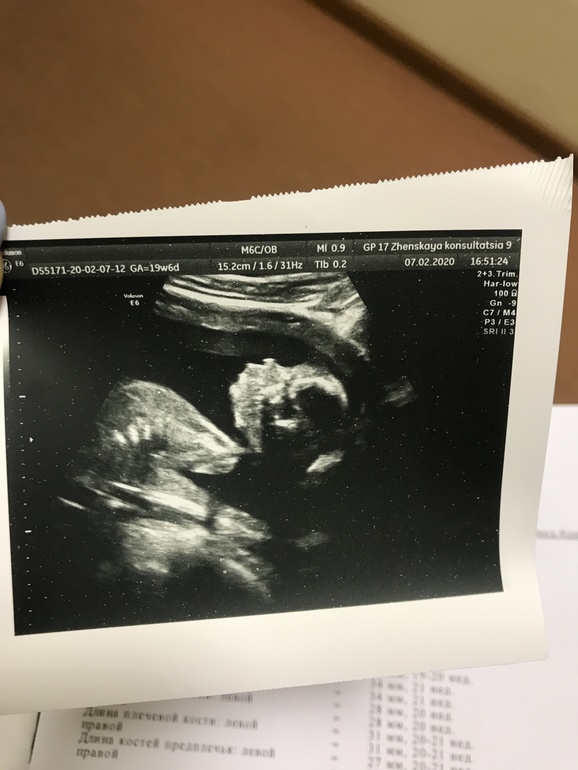

Она подробно прошлась по каждой косточке, органу, части тела моей малышки, которая, к слову капризная и вредная 😄 всё лежала вниз головой и не хотела показывать лицо, закрывалась, крутилась и вертелась.

Дочь с очень длинными ногами) срок 19+6 недель, а ноги на 21 неделю)

По всем параметрам ребёнок идеальный сказала 🥰😍 Все у неё по нормам и срокам, все органы) Врачиха такая - очень хорошая у вас Викторовна)) Папа говорит высокий чтоль раз ноги такие 😄😃 ну, папа 190 см у нас, я 170 см)

Все остальные параметры ниже на фото.